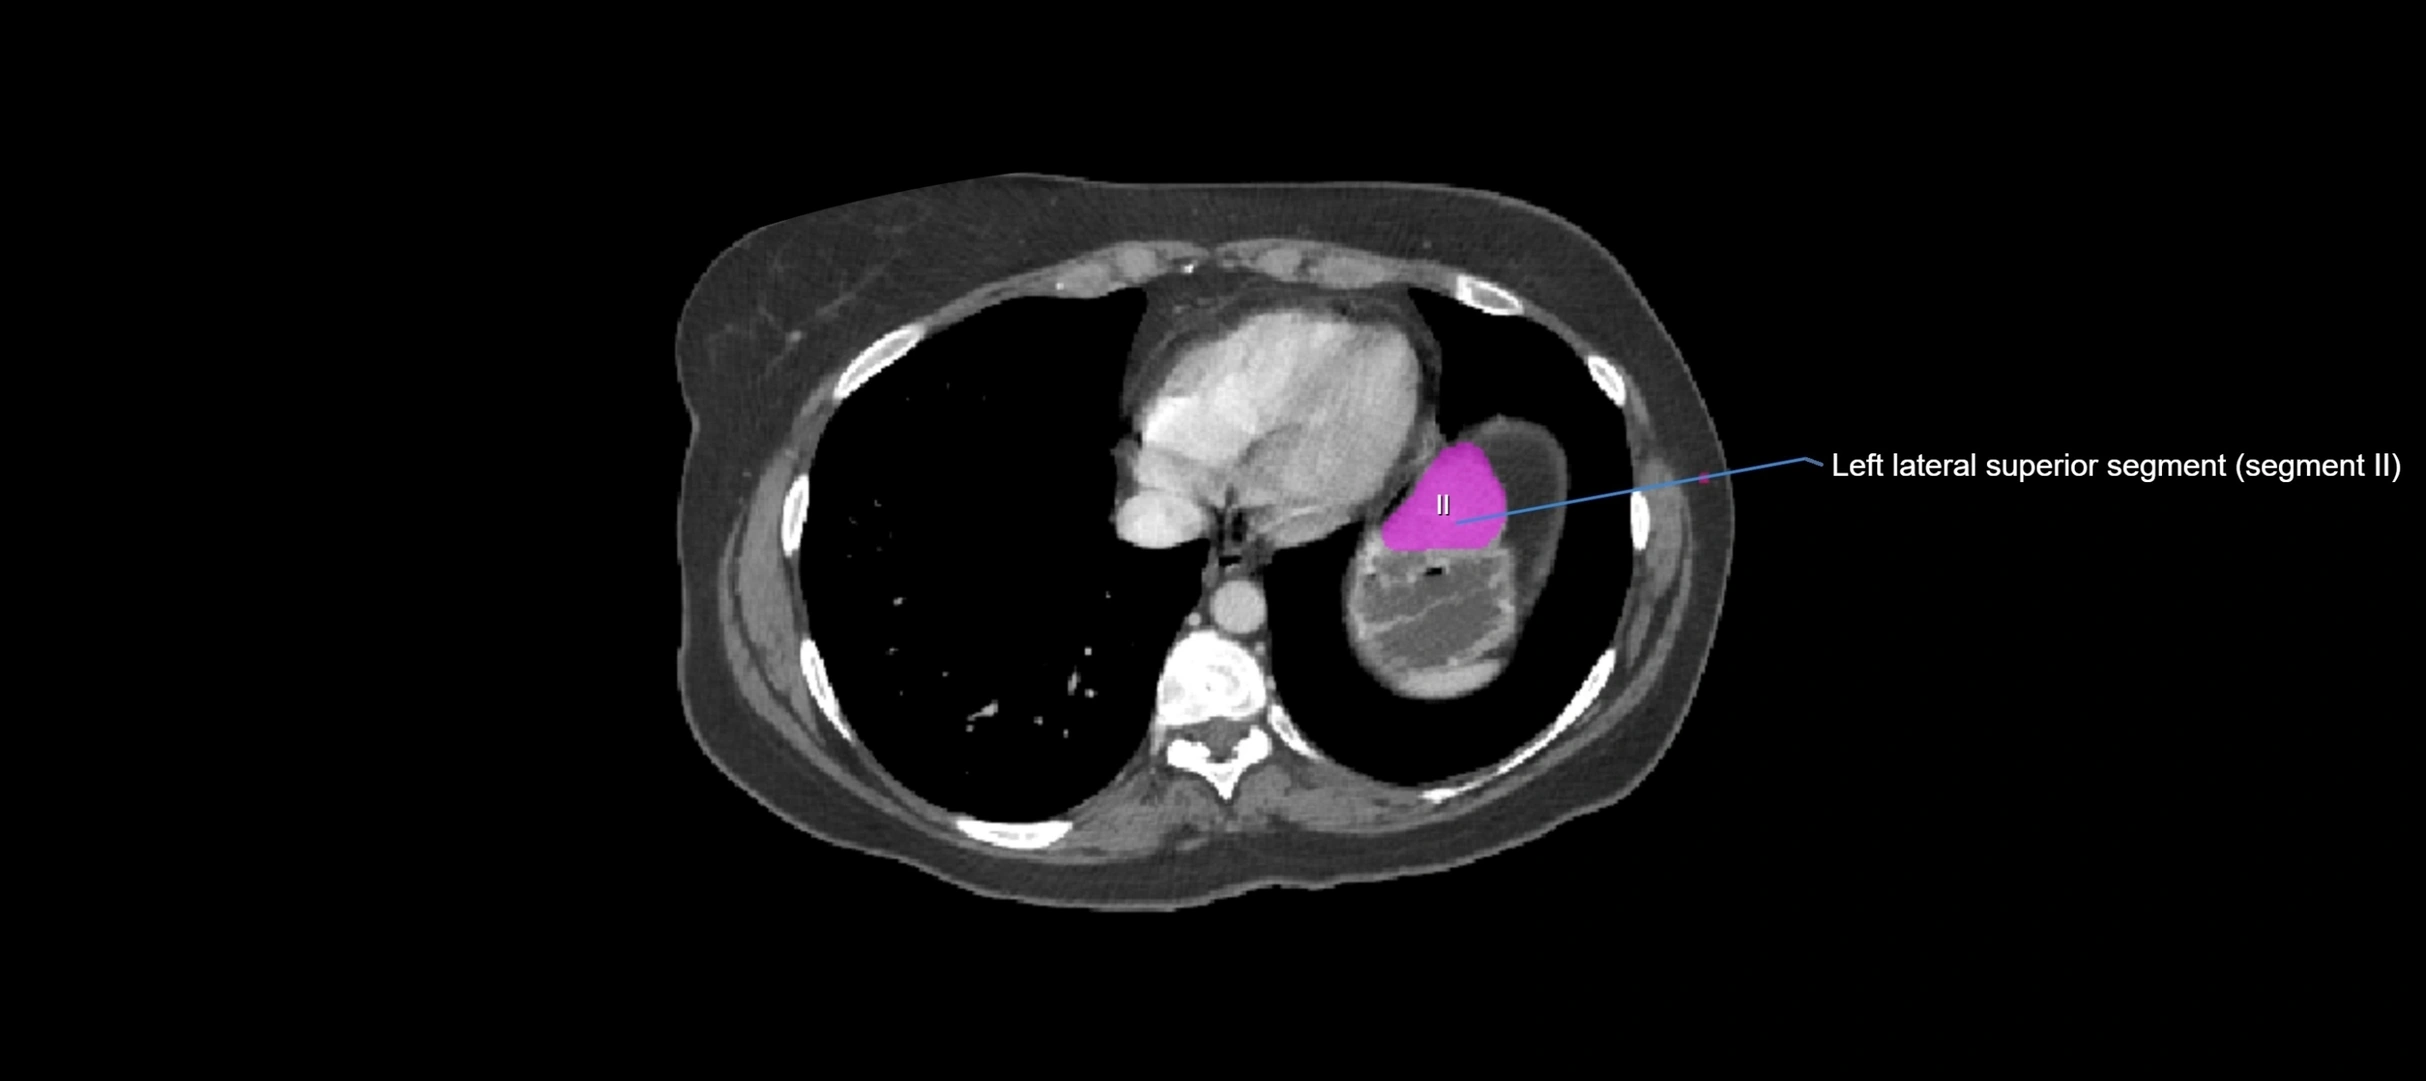

CT Image

image